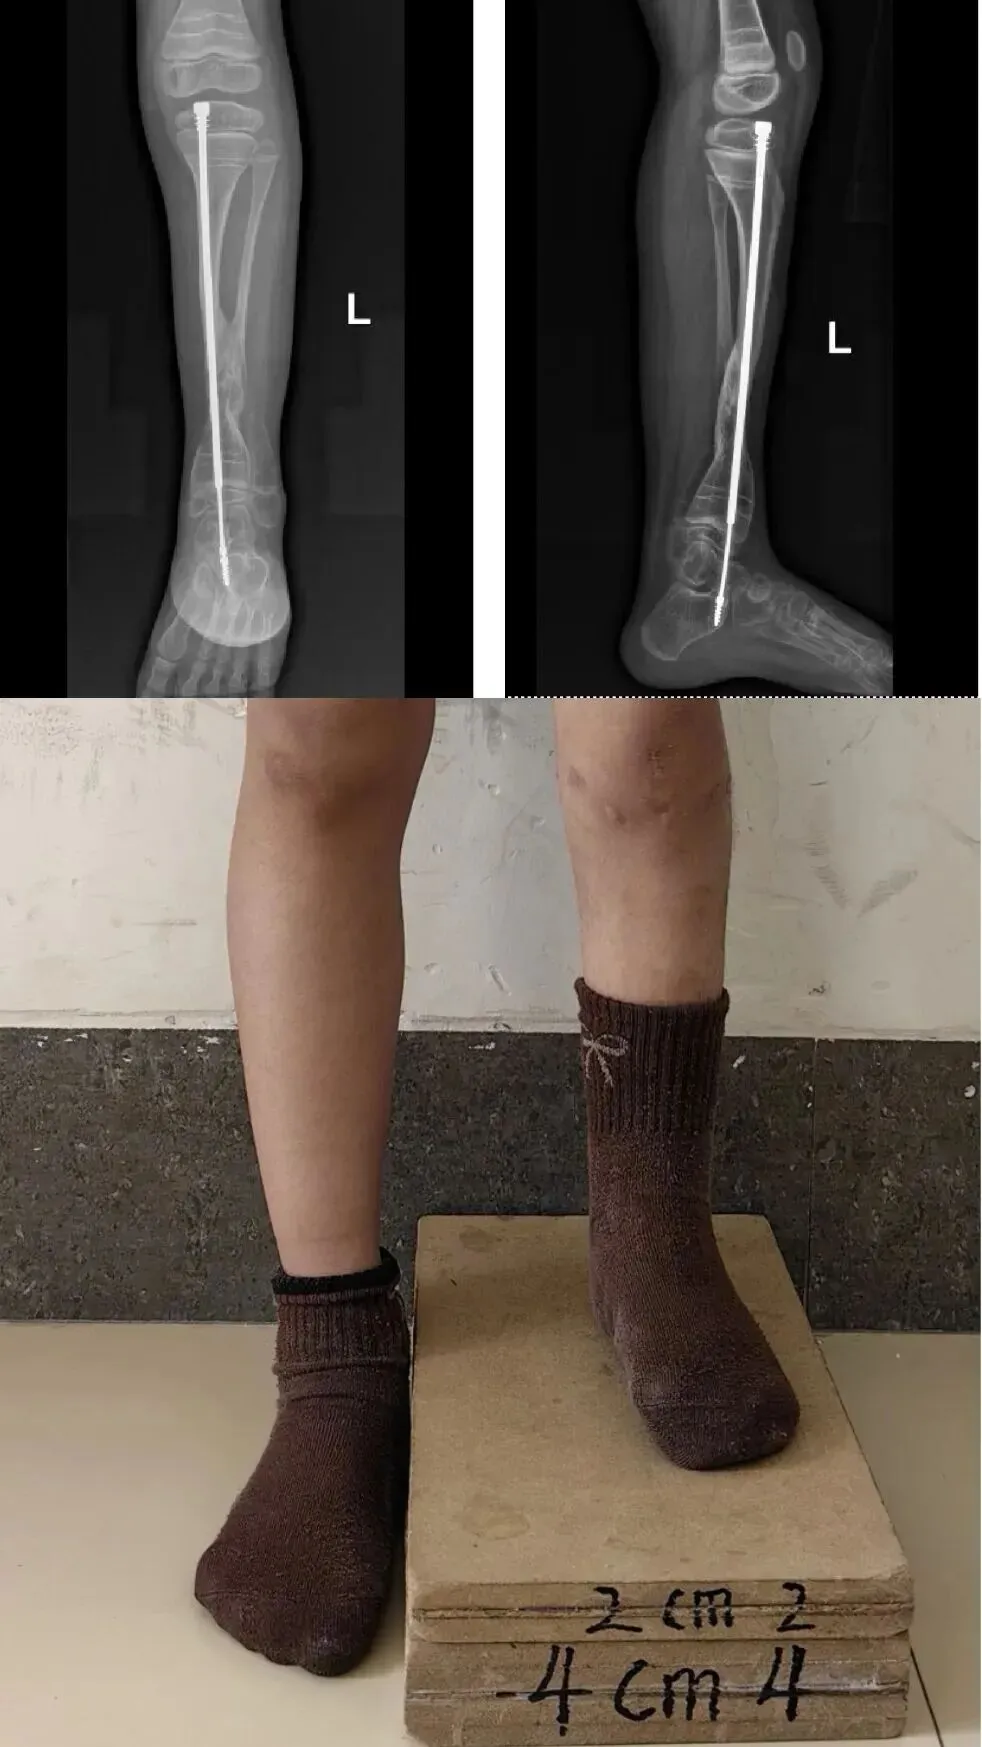

小雨父母多方辗转,带着她来到了郑州市骨科医院。接诊后,郑州市骨科医院小儿骨科的专家为小雨制定了手术方案:“假关节病灶切除+髓内棒固定+自体髂骨移植+环形外固定架加压”“切除病灶、取自体髂骨移植、植入髓内棒、安装外固定架……” 经过数小时的手术,“手术很成功”。

经过几个月的康复训练,复查显示:小雨的胫骨假关节已经实现骨性愈合,下肢力线完美,可以和正常小朋友一样,奔跑、玩耍了!